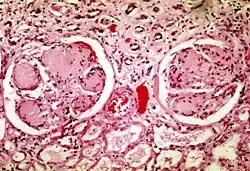

| Two glomeruli in diabetic nephropathy: the acellular light purple areas within the capillary tufts are the destructive mesangial matrix deposits. | |

Pathophysiologic abnormalities in diabetic nephropathy usually begin with long-standing poorly controlled blood glucose levels. This is followed by multiple changes in the filtration units of the kidneys, the nephrons. (There are normally about 750,000–1.5 million nephrons in each adult kidney).[8] Initially, there is constriction of the efferent arterioles and dilation of afferent arterioles, with resulting glomerular capillary hypertension and hyperfiltration particularly as nephrons become obsolescent and the adaption of hyperfiltration paradoxically causes further shear stress related damage to the delicate glomerular capillaries, further proteinuria, rising blood pressure and a vicious circle of additional nephron damage and decline in overall renal function.[9][10] Concurrently, there are changes within the glomerulus itself: these include a thickening of the basement membrane, a widening of the slit membranes of the podocytes, an increase in the number of mesangial cells, and an increase in mesangial matrix. This matrix invades the glomerular capillaries and produces deposits called Kimmelstiel-Wilson nodules. The mesangial cells and matrix can progressively expand and consume the entire glomerulus, shutting off filtration.[11]